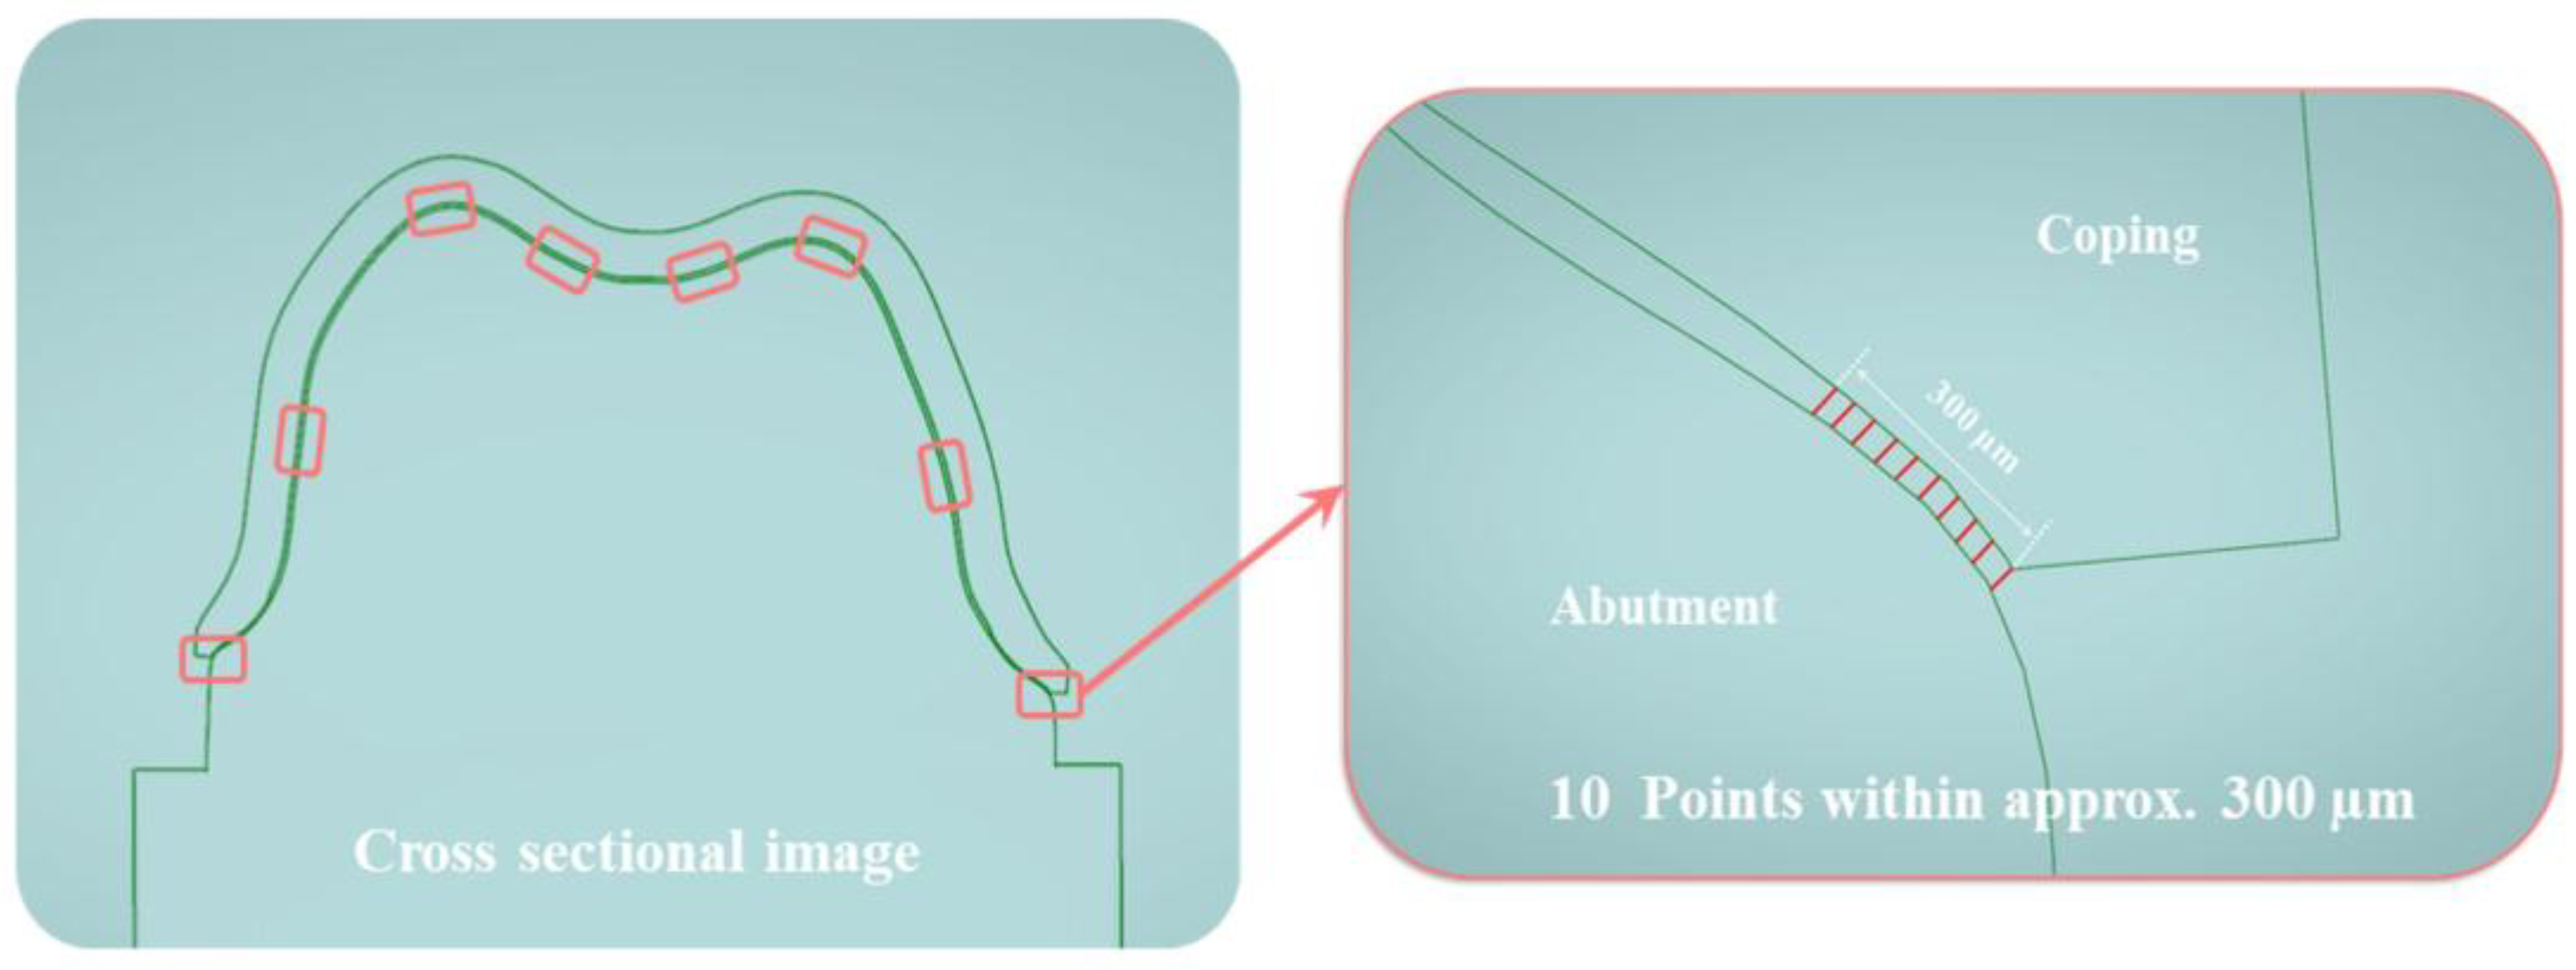

- The cross-sectional method (CSM): the CSM is a method in which after cementation, the desired part of the prosthesis is cut and measured with an optical or electronic microscope. Since the actual prosthesis is cut and measured, it has the advantage of allowing accurate measurement of the internal and marginal fit of the prosthesis. However, the disadvantages are that the method requires the samples to be destroyed, and the measurements cannot be made directly in the oral cavity [11,12,29].

2.2.1. Cross-Sectional Method (CSM Group)